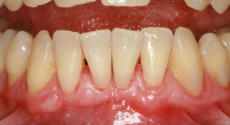

Mikrochirurgischer Wundverschluss

Gingivatransplantat fixiert

Zustand 3 Wochen post OP